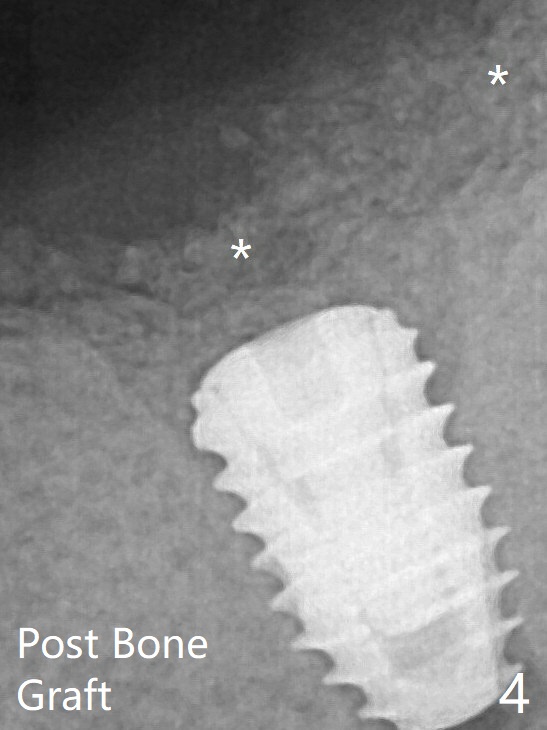

A 4.5x7.3 mm implant is initiatlly placed (Fig.3). The coronal defect is filled with allograft (Fig.4 *) following further placement of the implant. There is reorganized bone coronal to the healing screw 4 months postop (Fig.6), which is confirmed in uncovering. The overlying bone should be removed thoroughly for complete abutment seating.